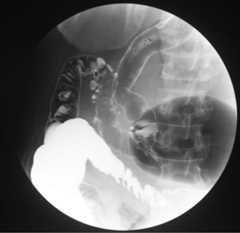

Barium enema findings

Barium enema showing a colon tumor as a defect in the sigmoid colon (arrow):

Around the sigmoid colon cancer, there are multiple colon diverticula in the sigmoid colon.

Image: “Barium enema findings” by Department of Surgery, Toyama City Hospital, 2-1 Imaizumi Hokubu-machi, Toyama 939-8511, Japan. License:CC BY 2.0